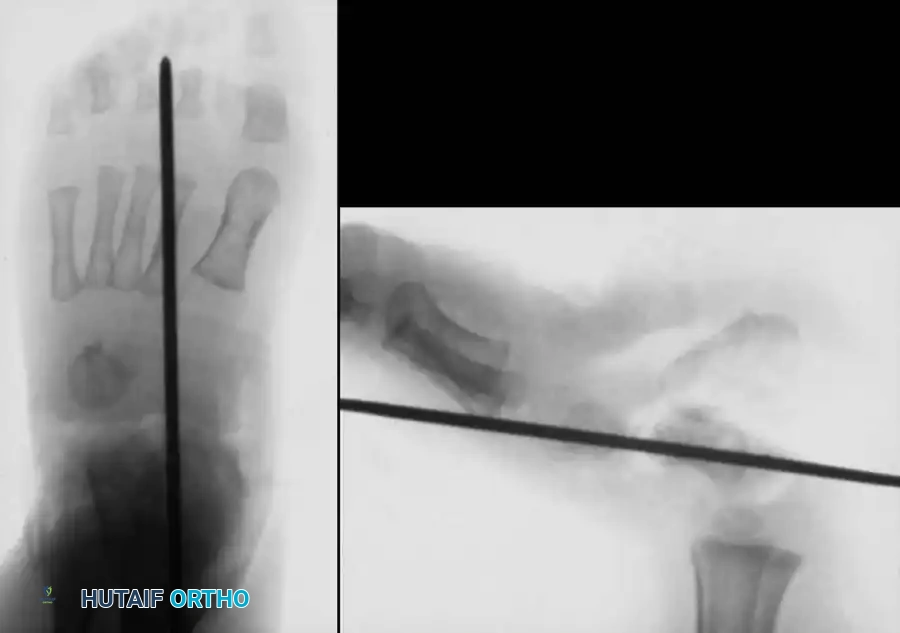

For infants and young children, a single-stage minimally invasive or limited-open approach has gained traction. Kodros and Dias described a highly effective technique utilizing a threaded Kirschner wire (K-wire) as a "joystick" to manipulate the vertical talus into an anatomic position.

Technique Overview:

1. A threaded K-wire is introduced axially into the vertical talus from a posterior approach.

2. The wire is utilized as a joystick to lever the talus out of equinus and medial deviation, elevating the talar head.

3. Simultaneously, the forefoot is plantarflexed and inverted to reduce the navicular onto the talar head.

4. Once anatomic reduction is confirmed fluoroscopically, the K-wire is advanced across the talonavicular joint to secure the reduction. Additional wires may be placed across the subtalar joint.

Outcomes: Mazzocca et al. demonstrated that a single-stage dorsal approach yields significantly shorter operative times, superior clinical scores, and fewer complications compared to traditional extensive posterior or combined approaches.